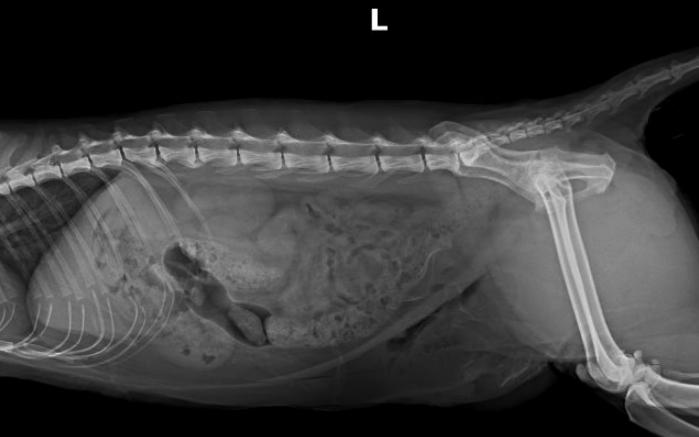

DR检查↓↓

Dr显示膀胱区域高密度影像,膀胱结石。

猫咪尿血来医院检查发现膀胱结石,当天安排了手术,手术前后影像对比,手术将结石全部取出↓↓